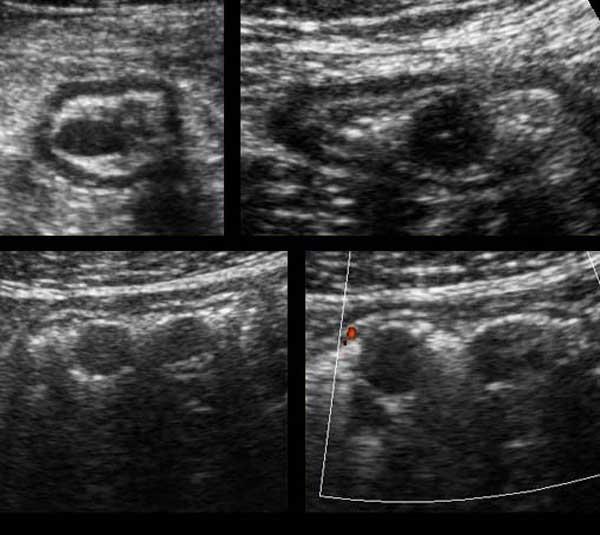

Colon

Hình ảnh dọc (trái) và ngang (phải) của đại tràng sigma rỗng ở bệnh nhân gầy.

Trong hình ảnh mặt cắt ngang, ba vùng dày lên cục bộ của lớp cơ (đầu mũi tên) đại diện cho ba dải cơ dọc kết tràng (đầu mũi tên).

Đại tràng bình thường chứa đầy phân (trái), trong quá trình co thắt (giữa) và trong quá trình giãn và nén (phải).

Normal colon wall thickness during compression is 3-4 mms.

Bóng lưng âm học của phân cản trở việc hiển thị siêu âm thành sau (bên trái).

Đại tràng được phân biệt với ruột non bởi vị trí, nội dung phân, nhu động thưa và lớp cơ ngoài dày với ba dải cơ dọc (tenia coli).

Lớp cơ của đại tràng sigma có thể thay đổi đáng kể về độ dày, chủ yếu do sự co bóp.

Sự dày lên vĩnh viễn của lớp cơ có liên quan đến sự phát triển của các túi thừa (mũi tên).

Sigmoid diverticulosis in four different patients.

Các túi thừa chứa đầy phân được quan sát rõ nhất khi đại tràng co lại.

Chúng biểu hiện là các cấu trúc phản âm sáng với bóng cản âm ở bờ ngoài của đại tràng.

Lưu ý độ dày thay đổi của lớp cơ ở bốn bệnh nhân này.